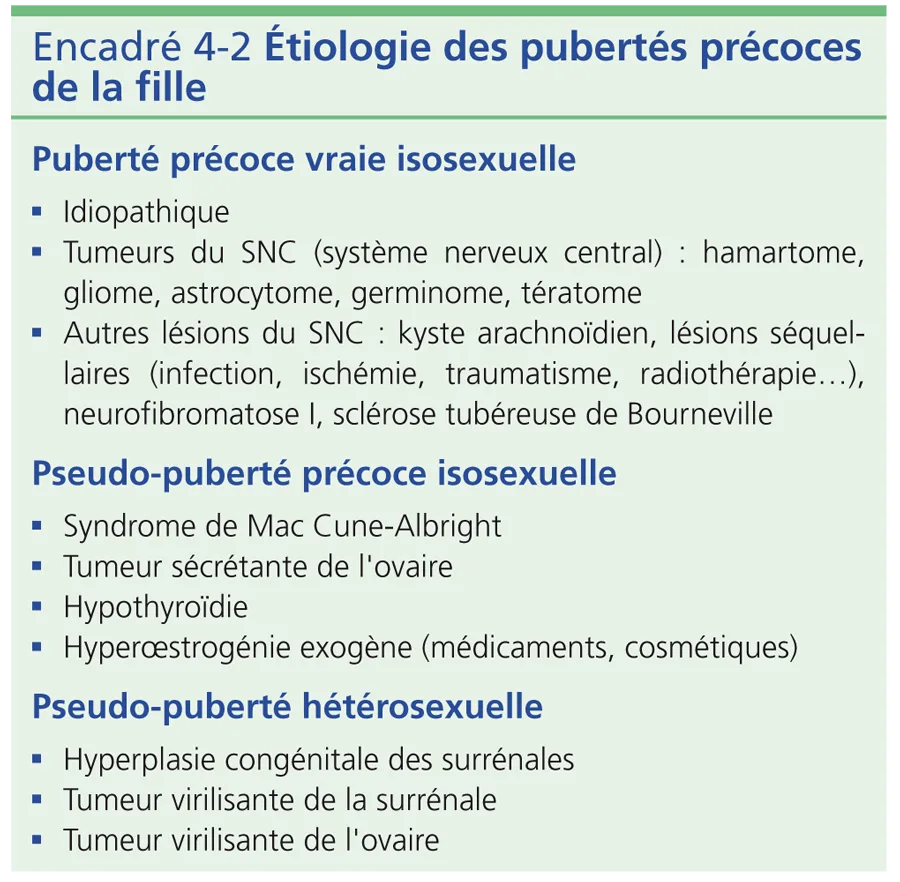

Les gliomes sont possibles, survenant isolément ou souvent dans le cadre d’une neurofibromatose. Les autres causes sont résumées dans l’encadré 4-2.